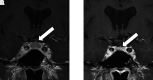

A false pituitary tumor describes pituitary enlargement due to intracranial hypotension. Reported previously primarily in the neurological literature, we present this case referred to endocrinology for evaluation of a pituitary mass. A 24-year-old male was referred to endocrinology for evaluation of pituitary enlargement without a hypo-enhancing lesion on magnetic resonance imaging (MRI). The main symptom reported was headache that was worse in the standing position and in the afternoon. He had no symptoms or signs of pituitary mass-effect, or hormone excess or deficiencies. Past medical history was relevant for a history of nerve schwannoma status post resection with subsequent spinal fusion. Biochemical evaluation of pituitary hormones was normal. Upon review of his pituitary MRI, other abnormalities seen were suggestive of intracranial hypotension. Based on his history and imaging findings, he was diagnosed with intracranial hypotension causing a "false pituitary tumor" rather than pituitary enlargement or abnormality. Further evaluation revealed multiple spinal leaks that were patched. His symptoms subsided within a few days of repair. Endocrinologists should be aware of the possible misdiagnosis of a pituitary mass due to intracranial hypotension.